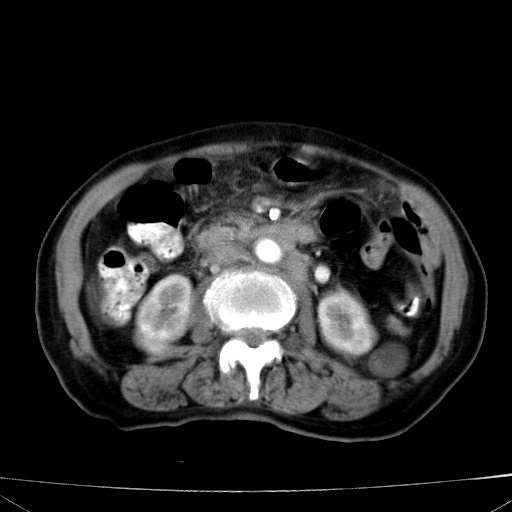

网站人气太旺!昨天的帖子就沉到海底,只好再发贴!ct18338:女 78岁,肝胆病变,已增强,再会诊!原帖链接:http://www.radida.com/bbs/forum.php?mod=viewthread&tid=50032

1)考虑胆囊癌侵犯肝脏并肝门区、腹膜后及右侧膈角后淋巴结转移。2)肝左叶近肝顶部囊肿。3)肝左叶肝内胆管结石。4)左肾近下极囊肿。

1)考虑胆囊癌侵犯肝脏并肝门区、腹膜后及右侧膈角后淋巴结转移。2)肝左叶近肝顶部囊肿。3)肝左叶肝内胆管结石。4)左肾近下极囊肿。支持